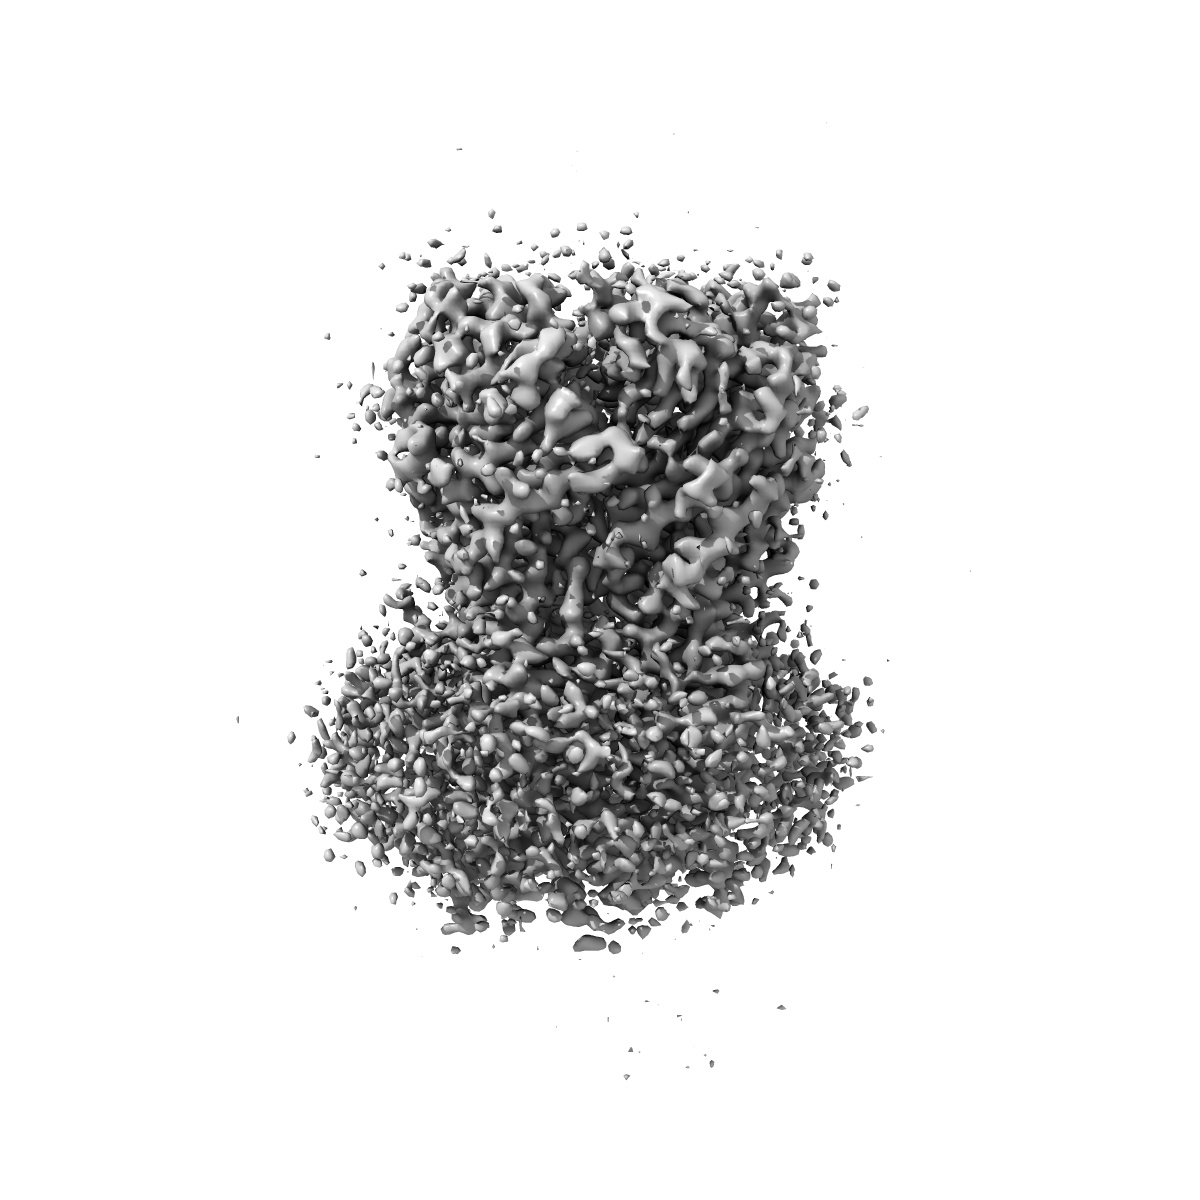

Cyro-EM structure of human Glycine Receptor alpha2-beta heteromer, strychnine bound state, 3.8 Angstrom

Sample Organism: Homo sapiens

Sample: Glycine receptor alpha2-beta heteromer with strychnine, 3.8 Angstrom

Fitted models: 7l31

Characterization of the subunit composition and structure of adult human glycine receptors

Yu H, Bai X-C, Wang W

(2021) Neuron , 109 , 2707 - 2716